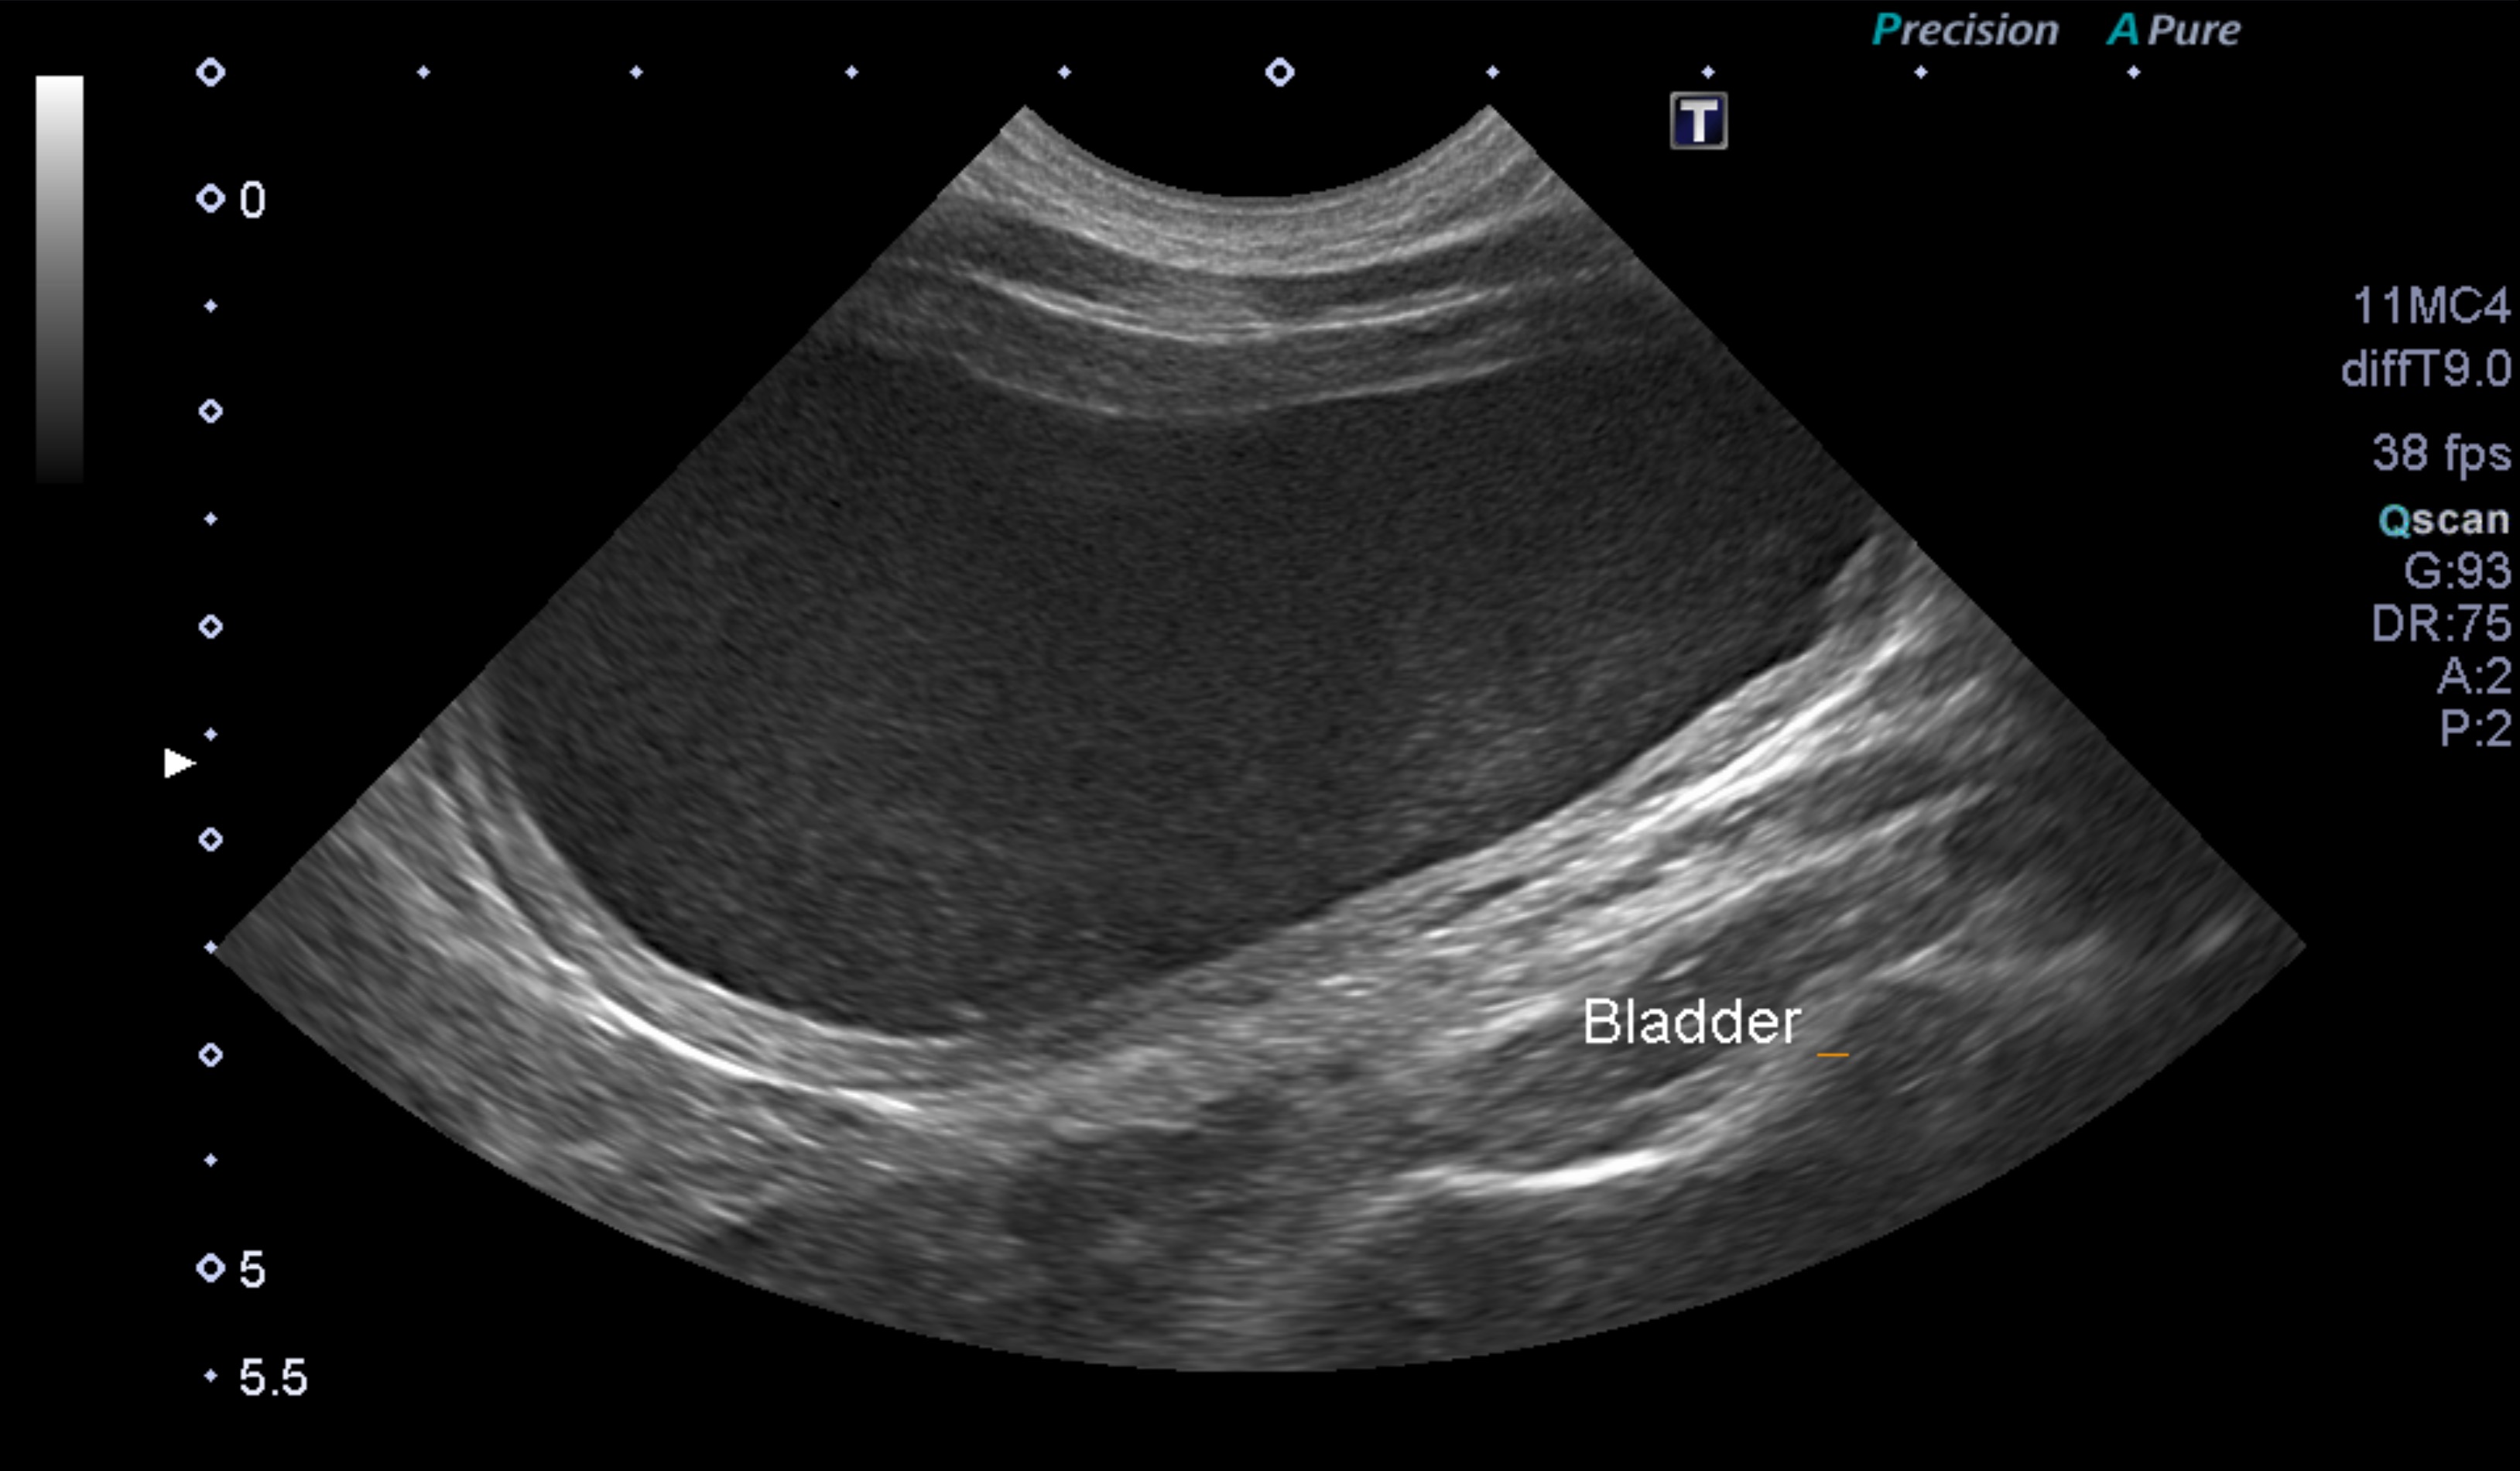

超音波検査で膀胱内に多量の尿が認められ、膀胱内の尿はモザイク様に観察されました。

超音波検査でも、膀胱内の尿が綺麗になっているのが確認できます。